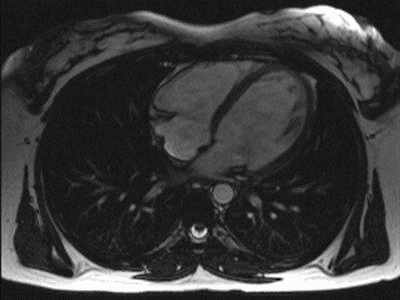

MRT-Aufnahme eines schlagenden Herzens 2, GIF-Animation

Big Bang 8

Link

GIF

MRT-Aufnahme eines schlagenden Herzens 1, GIF-Animation

Herzschlag im Kernspintomographen, GIF-Animation